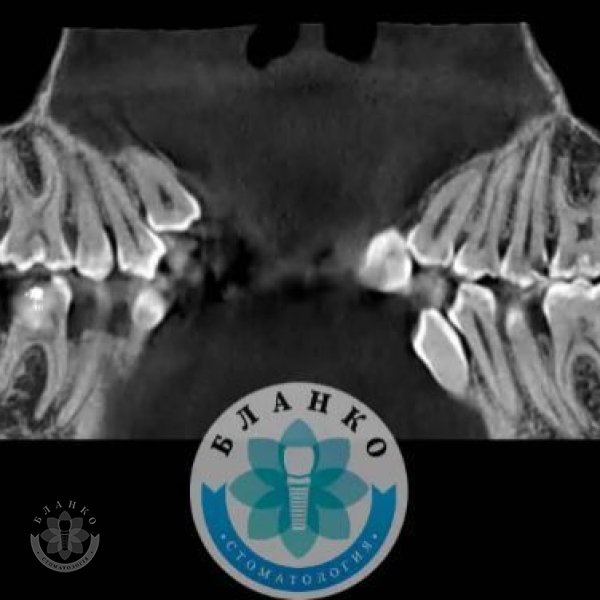

Глибока руйнація😳👿

Чим глибше під ясна зруйнований зуб — тим складніше він піддається адекватному відновленню☝

У даному клінічному випадку два зуби відновлено культевими вкладками, виготовлено коронки з оксиду цирконію, третій зуб відновлено за допомогою прямої фотополімерної реставрації 😁👍